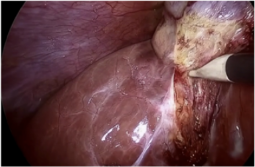

Refer to caption

((a)) Instrument flare

((b)) Partial occlusions by blood

((c)) Smoke-induced occlusion

((d)) Underexposed regions

((e)) Motion blur

((f)) Multiple instruments

((g)) Partial occlusion by organ

((h)) Transparent instrument

Figure 7: Key challenges in surgical video analysis include photometric artifacts (e.g., blurriness, specular reflections), occlusions from blood and tissue deformation, limited camera view, and tool similarity. These complexities hinder robust localization and segmentation, emphasizing the need for advanced Foundation Models. Image adapted from (Cerón et al., 2022).

The domain of surgical video analysis presents unique challenges that hinder robust localization and segmentation of surgical instruments, as shown in Fig. 7. Unlike natural images and videos, surgical frames are characterized by high tissue deformations and frequent occlusions caused by the presence of blood and multiple artifacts on the instruments. Photometric artifacts, as identified by (Ni et al., 2020a), can significantly degrade the performance of segmentation models. Some of the additional complexities include: